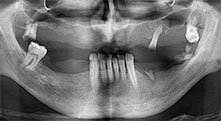

Bratu: Utilizamos los insertos de forma rutinaria para la extracción de injertos óseos y la ranuración de las crestas alveolares. También utilizamos las Piezomed B6/B7 para practicar osteotomías en dientes retenidos y no retiramos implantes que pueden conservarse. Todas estas son indicaciones que requieren cortes profundos y limpios.

¿Podría describirnos brevemente cómo procede, por ejemplo, a la hora de mover injertos óseos destinados a trasplantes?

Bratu: Preferimos realizar las osteotomías en la línea oblicua externa de la cara posterior del maxilar inferior, y no en la región situada entre los orificios. Tras realizar una incisión en los tejidos blandos, utilizamos las nuevas sierras para definir el contorno de la osteotomía. De este modo, conseguimos una preparación completa en prácticamente el 80 por ciento de los casos. Por otro lado, en algunas ocasiones también utilizamos otros insertos piezoquirúrgicos, así como un cincel para mover el injerto. Para nosotros, esta es una técnica de intervención muy eficaz.